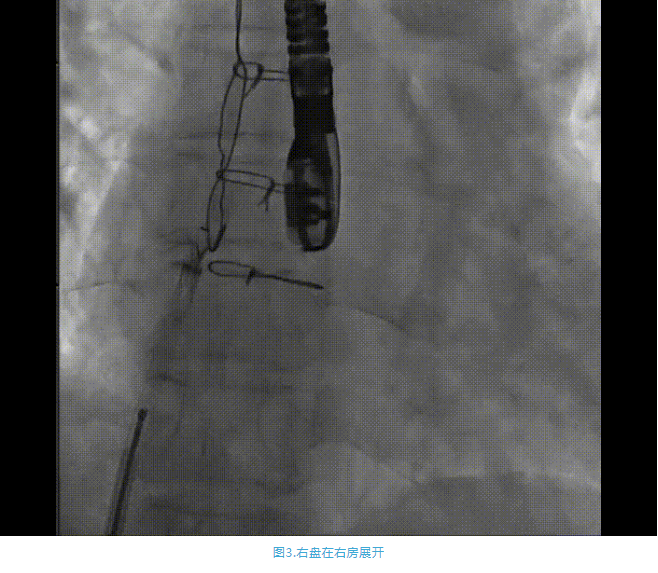

術(shù)中首先在局麻下穿刺股動(dòng)脈、股靜脈,完成心導(dǎo)管檢查評估后轉(zhuǎn)為全麻,在食道超聲引導(dǎo)下穿刺房間隔,穿刺成功后將加硬導(dǎo)絲送入左上肺靜脈建立軌道,根據(jù)患者病情行球囊預(yù)擴(kuò)張后植入6mm孔徑房間隔造孔支架,經(jīng)透視及食道超聲評估支架左右盤展開良好,夾持于房間隔兩側(cè),固定穩(wěn)定、位置良好,食道彩超顯示房水平右向左為主分流,分流孔直徑符合預(yù)期大小,心導(dǎo)管檢查評估達(dá)到預(yù)期效果,釋放造孔支架。術(shù)后12h患者下床活動(dòng),恢復(fù)順利,擬于近日完善術(shù)后評估后出院。